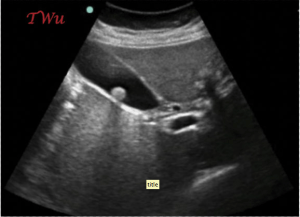

The right upper quadrant view above shows a gallstone – but is that what is causing her pain? As we become more and more savvy with bedside ultrasound, we will start sounding like our radiologist friends, and Ill leave you with exactly that: “Correlate clinically.” Read the story, as it will highlight not only bedside US utilization, but education pearls on cholelithiasis and right upper quadrant bedside ultrasound pitfalls.